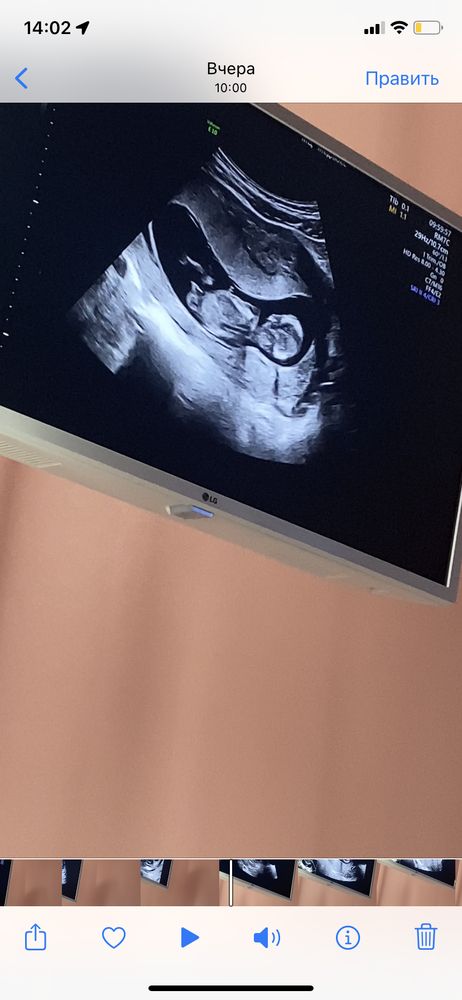

1 скрининг

Всем привет ) вчера прошла 1 скрининг , по месячным срок 12.1, по длине 12.5, все хорошо 🥰 недавно писала пост на определение пола по бугорку , так вот , в этот раз по видео высматривала бугорок , и он все таки перпендикулярен , но врач , сказал , что в разной плоскости , наклон будет разным , поэтому на таком сроке даже не предполагают , будем ждать второй скрининг )

Проходила мимо поста,сразу подумала 'ой, мальчишечка"😁мальчик тут,однозначно )))

Счастье Любит Тишину, да , по бугорку похоже на мальчика ))

Но думаю , может ракурс не удачный , или это нога 😂 С других ракурсов ,больше как девочка

Кристина, да уж)) ну все равно мне кажется больше к мальчику,чем к девочке